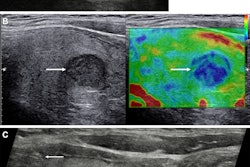

Radiology researchers continue to explore how machine-learning techniques can address current limitations in risk stratification and disease prediction. TI-RADS, which offers structured criteria for assessing thyroid nodules, is susceptible to interobserver variability, the researchers noted. This leads to inconsistent clinical decision-making.

With this in mind, Li and colleagues developed their deep learning models, which combined clinical and radiological features with deep imaging features extracted from ultrasound scans using EfficientNet-B0. The latter is a convolutional neural network (CNN) that is trained on more than one million images from the ImageNet database.

The study included 580 patients with thyroid nodules categorized from TI-RADS 2 to 5. The researchers reported that the clinical models achieved strong predictive ability.